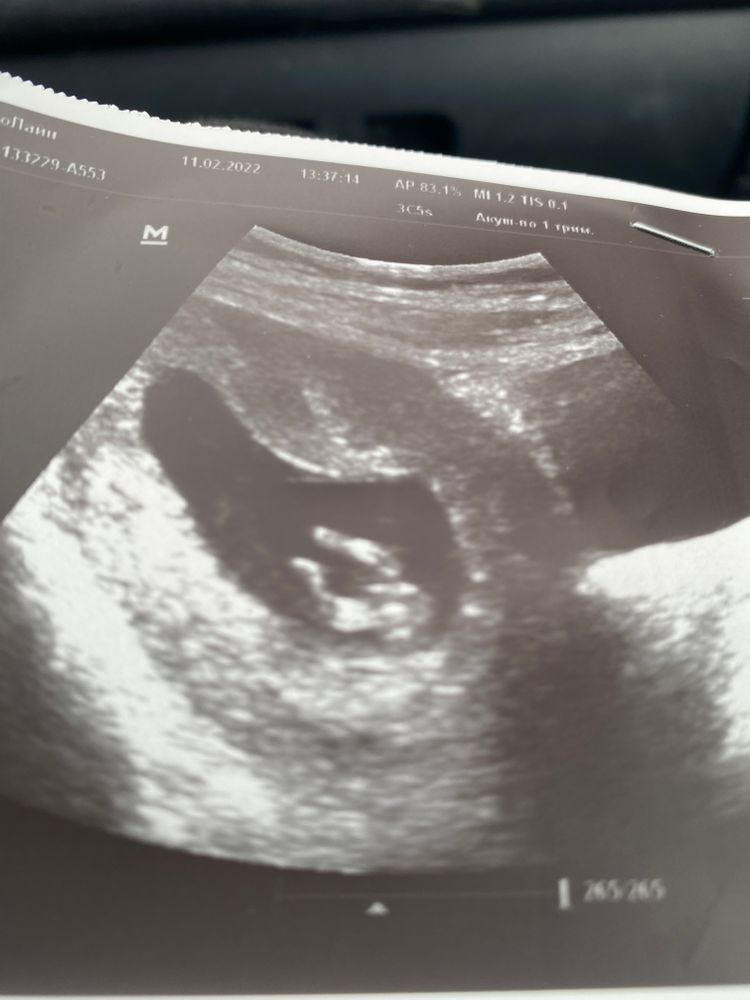

Узи 10+3 недель, ведь рано для определения пола

На таком сроке половой бугорок есть и у мальчиков, и у девочек, а все зависит от уголка наклона. Мне в 12+2 сказали пол (но я делала нипт до этого и врач не ошиблась), но смотрели еще в 3д.

У меня в 11,1 был в малыша прям девчачий половой бугорок, а когда снизу врач смотрела, то сказала, что пока ничего не торчит. На скрининге в 12,1 уже половой бугорок торчал вверх, и в 15 недель врач по узи сказала, что мальчик, но я знала, что у меня мальчик, потому что в 9,5 недель кровь сдавала на определение пола. Поэтому я бы на таком сроке на узи пока ну совсем не ориентировалась бы.

На 1 скрининге однозначно могут увидеть, в 10 недель не уверена, что могут определить...